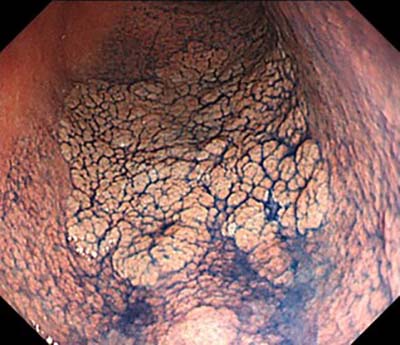

大腸ポリープ

- 大腸癌、大腸ポリープ

- 大腸ポリープ:粘膜切除術(EMR)、cold polypectomy